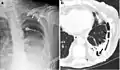

A fibrothorax can typically be diagnosed by taking an appropriate medical history in combination with the use of appropriate imaging techniques such as a plain chest X-ray or CT scan.[3] These imaging techniques can detect fibrothorax and pleural thickening that surround the lungs.[7] The presence of a thickened peel with or without calcification are common features of fibrothorax when imaged.[3] CT scans can more readily differentiate whether pleural thickening is due to extra fat deposition or true pleural thickening than X-rays.[3]

If a fibrothorax is severe, the thickening may restrict the lung on the affected side causing a loss of lung volume.[7] Additionally, the mediastinum may be physically shifted toward the affected side.[3] A reduction in the size of one side of the chest (hemithorax) on an X-ray or CT scan of the chest suggests chronic scarring.[6] Signs of the underlying disease causing the fibrothorax are also occasionally seen on the X-ray.[6] A CT scan may show features similar to those seen on a plain X-ray.[7] Lung function testing typically demonstrates findings consistent with restrictive lung disease.[6]